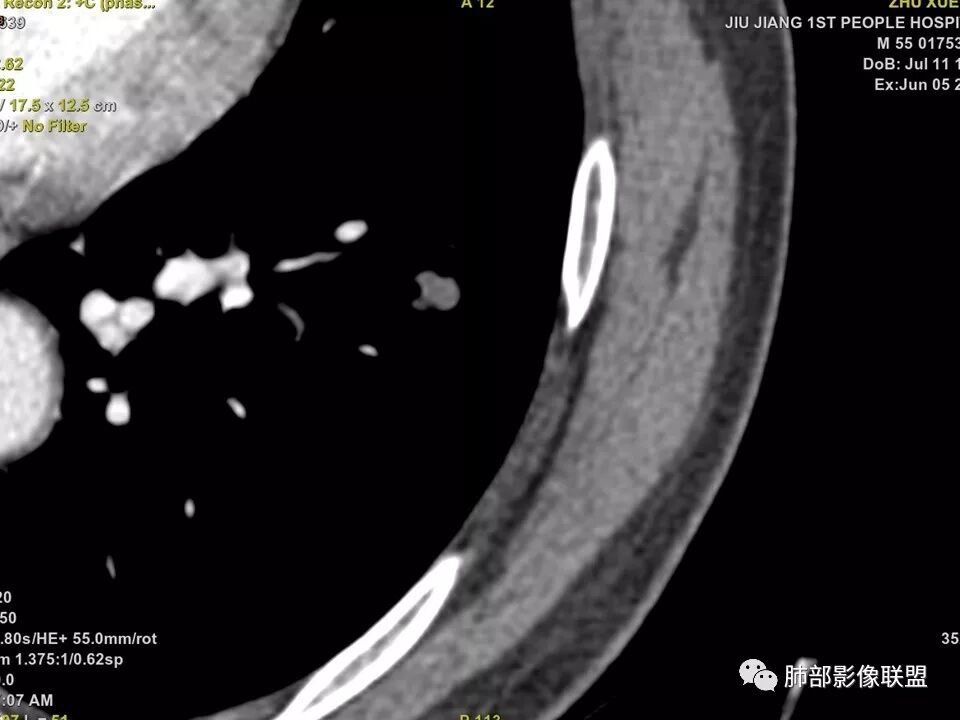

边缘有光滑,有圈黑晕,强化弱,似乎有脂肪密度,支气管截断的部位很自然,没有鼠尾状狭窄,考虑软骨型错构瘤?

这个支气管开口位置,如果是肿瘤应该有管壁浸润,也应该有膨胀感,这个没有,不像恶性肿瘤的支气管截断

病灶部分平直丶内收,有脂肪密度,不强化支持错构瘤。部分病灶有结节堆积感,分叶,与支气管、肺动脉关系密切,需鉴别腺癌。不强化进一步结核结节。

左肺下叶前内基底段结节,轮廓凹凸不平,局部边缘平直,密度不均,近段支气管阻塞,增强前后CT值无明显变化,考虑肉芽肿,结核?腺癌代排

左肺下叶前基底段结节,病灶边缘分叶,边缘平直,u型征,可见气管截断,增强可见病灶边缘血管,平扫ct值低,轻度强化。考虑良性病变。

不是假象,是真的堵了,我工作站薄层做了气管曲面重建,仿真内窥镜也显示堵了

也咨询了病理科老师,肺软骨瘤来源于支气管透明软骨,理论上可以从黏膜下,突向支气管腔内生长,对支气管造成压迫性的阻塞。影像上和软骨瘤样错构瘤没法区分

典型CT特征包括:(1)圆形或椭圆形边界清楚的病灶。(2)大小1~4cm,有轻微分叶改变。(3)较均匀的软组织影,多伴有钙化。(4)无毛刺,卫星灶及肺门或纵隔淋巴结肿大。(5)CT增强扫描无强化或轻度强化,其强化可能与软骨瘤间质中的薄壁血管或周围慢性炎症反应有关。